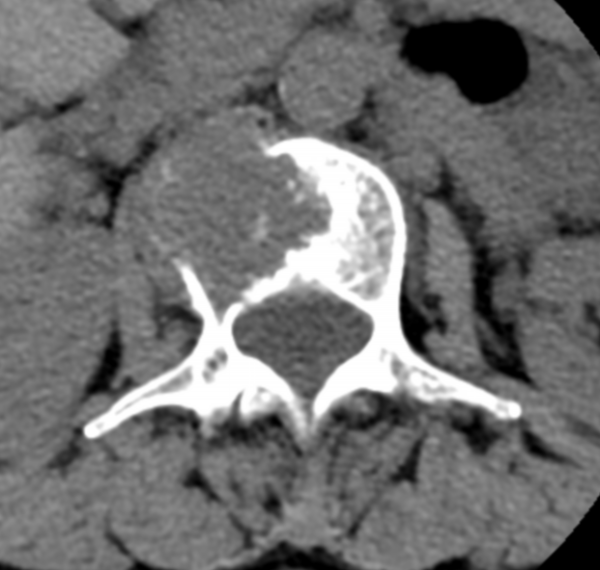

文章配圖

△ 術前CT:腰2椎體骨質破壞,伴周圍軟組織腫脹,考慮骨轉移瘤。